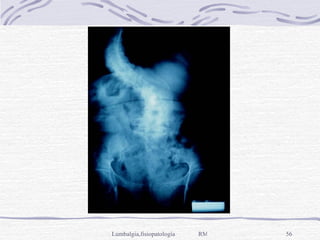

Aneurisma de la aorta,  al erosionar la pared anterior de un cuerpo vertebral; Rx: erosión y pérdida del muro anterior de la vértebra, con dilatación aórtica, la angiografía lo determina.  Insuficiencia vascular intrínseca,  por várices intracanaliculares, TAC y RM masa ocupativa, flebografía es de elección

Aneurisma de laaorta, al erosionar la pared anterior de un cuerpo vertebral; Rx: erosión y pérdida del muro anterior de la vértebra, con dilatación aórtica, la angiografía lo determina. Insuficiencia vascular intrínseca, por várices intracanaliculares, TAC y RM masa ocupativa, flebografía es de elección